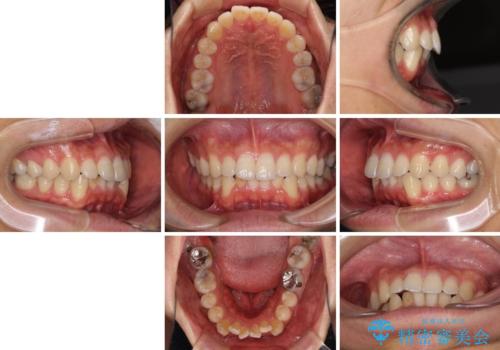

口が少し閉じにくい インビザラインによる非抜歯矯正

- 口元の突出感を治したいとのことで来院された患者様です。

上下顎ともにIPR(歯と歯の間を削る)と歯列全体の拡大によって口元が引っ込むように設計し、インビザラインにより治療を行うこととしました。

抜歯をして口元を下げなければならないほど出っ歯ではなかったため、少しずつ治療ゴールを変更しながら仕上げていきました。

気になっていた前歯の飛び出した印象は、最終的にはスッキリと引っ込み、大変満足していただきました。